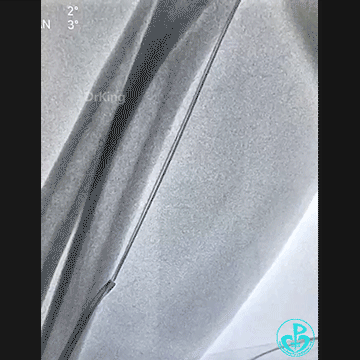

桡动脉鞘进JR 4.0指引导管,送入Sion,沿Sion送入2.5mm球囊,球囊越过穿刺导丝到达远端,6atm“打起来”后回撤,导丝被球囊带回来到指引导管口附近。

持续球囊锚定导丝调整指引导管角度,对准后回拉球囊,将导丝带入指引导管内,最后连同指引导管一起成功拉出。